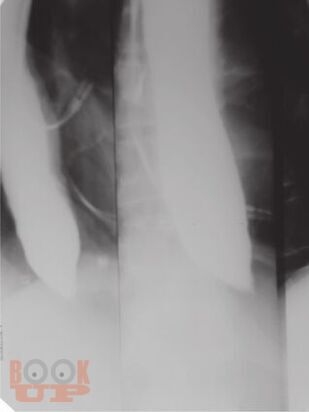

В основу издания положено собрание избранных клинических разборов, регулярно проводимых в ЦНИИ гастроэнтерологии. Многие из приведенных наблюдений являются уникальными, представляя собой либо клинический раритет, либо описание необычного течения давно известного заболевания, либо недавно описанное новое заболевание, прижизненный диагноз которого стал возможным благодаря внедрению новейших диагностических технологий. Особое внимание уделено и уникальным коррекционным вмешательствам.